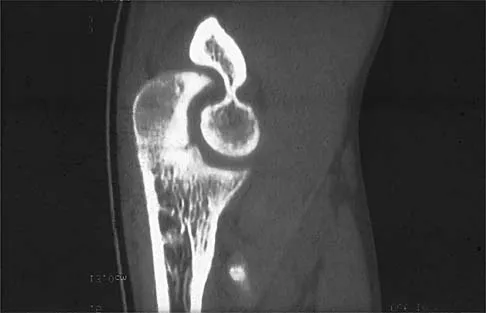

Following a fall from a height of 5 feet, a patient reports pain along the lateral border of the foot. The CT scan shown in Figure 54 indicates what pathology?

Explanation

The CT scan reveals an avulsion of the dorsal beak of the anterior process of the calcaneus. This common fracture is an avulsion of the origin of the bifurcate ligament, which runs from the anterior calcaneal process to both the cuboid and the lateral aspect of the navicular. An inversion mechanism is common, and the fracture is often missed in evaluation for a suspected ankle sprain. MRI may be useful in the diagnosis of these occult injuries, and suspicion should be present when tenderness exists over the superior portion of the anterior process of the calcaneus.